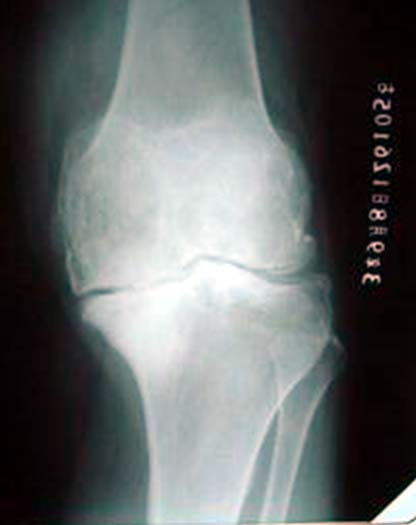

图:膝关节软骨碎裂、磨损,双膝内翻,X线片显示关节间隙消失

病例一、患者男性,76岁,双膝疼痛10年,屈伸受限,下蹲困难。线片显示双膝骨关节炎改变,关节间隙已经消失。严重膝内翻畸形。

患者女性,56岁,双膝骨关节炎15年,双膝屈伸受限,下蹲困难。线片显示膝骨关节炎改变,关节间隙已经消失。膝内翻畸形。行分期人工膝关节置换术。